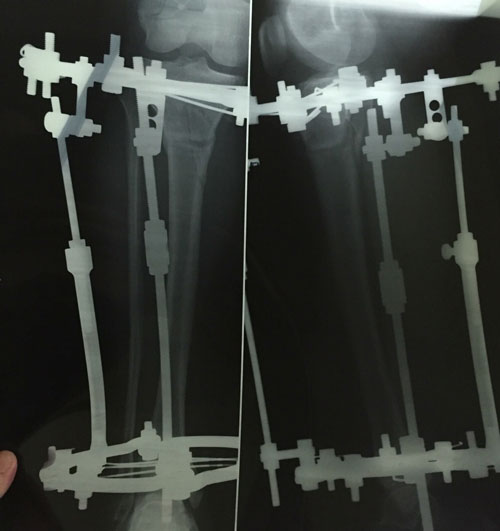

Ножки супер! разрешено всё без ограничений, все нагрузки: спорт, фитнес, каблуки любых размеров - Вам очень они пойдут! Нельзя: беременеть в течении первых 6 месяцев с момента снятия аппаратов!

Не забывайте про наш форум, высылайте фото ножек, пишите отзывы, нам это важно, это наша работа - искусство, которым мы гордимся!